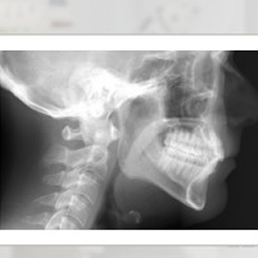

Badanie RTG czaszki pozwala ocenić zgryz Pacjenta oraz pobrać wymiary niezbędne przy wyborze aparatu ortodontycznego.

- RTG cefalometryczne (cefalometria) – wykorzystywane w ortodoncji. Pokazuje profil czaszki i ustawienie zębów względem struktur kostnych twarzoczaszki. To jedno z podstawowych badań przy planowaniu leczenia wad zgryzu.